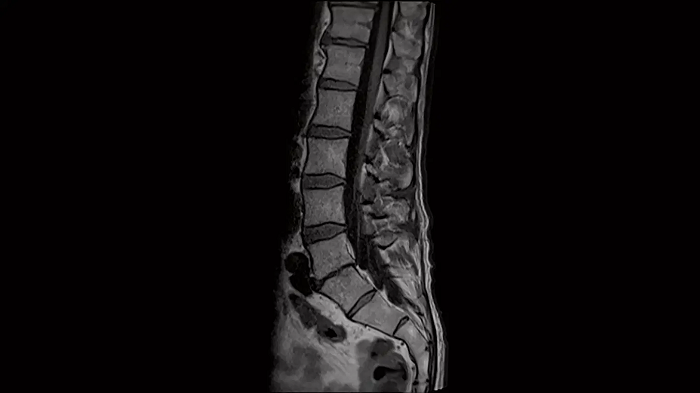

Spine

L-Spine - T1 TSE

Optimal depiction of the lower spine with T1 TSE imaging using the Spine Coil.

Image Courtesy: University Hospital Erlangen, Germany | Image-ID: 4aaaa0376